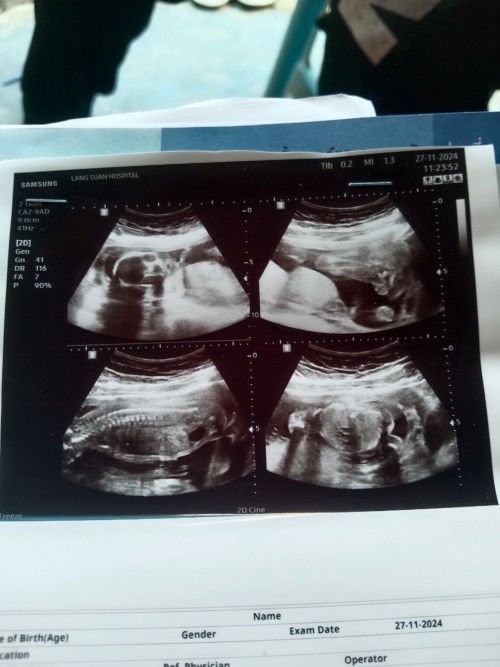

ทายเพศเล่นๆกันคะ ผู้หญิงหรือผู้ชายน่าา🫣

แม่ๆรู้ไหมคะว่าหนูเพศอะไร ดิ้นเก่งมาก จิ๋วแต่แจ๋วมากเลยน่ะ 20+5w #ทีมเมษายน68 #ทายเล่นๆกันค่ะแม่ๆ